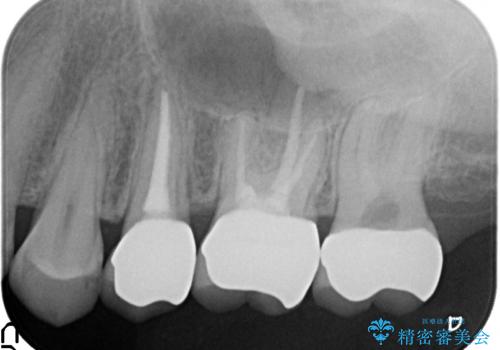

- 左上の歯が痛くてものが咬めないといらっしゃった方の症例です。

左上6は自発痛および持続痛を認めたため根管治療後、オールセラミッククラウンによる補綴を行いました。

左上7は冷水痛のみだったため、慎重に虫歯の除去を行い症状がないことを確認後、オールセラミッククラウンによる補綴を行いました。

左上5は再根管治療後、オールセラミッククラウンによる補綴を行いました。

- オールセラミッククラウン…¥100,000×3、仮歯…¥10,000×3、ファイバーコア…¥20,000×2費用は治療当時の料金となります

今回用いたオールセラミッククラウンはジルコニアフレームという白い素材の上にセラミックを盛っているため、審美性が非常に高いのが特徴です。

また、ジルコニアは人工ダイヤモンドの材料にも使われているほど高い強度を持っており、そのためオールセラミッククラウンは審美性だけでなく、奥歯やブリッジの補綴も可能とするクラウンです。